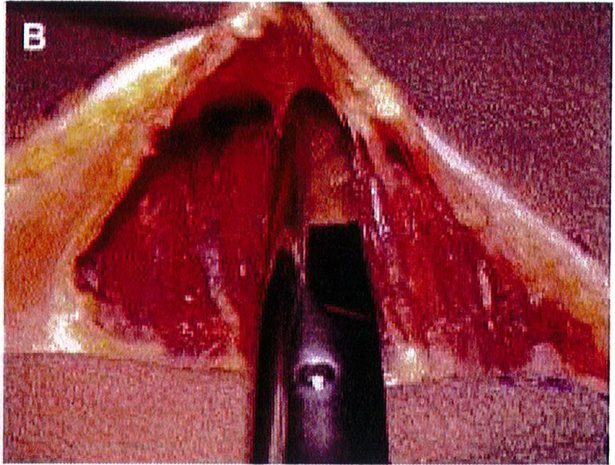

Hình. 9. Đánh dấu các mốc giải phẫu quan trọng. (A) Đường rạch cân cơ mông lớn bắt đầu từ bờ ngoài xương cùng (B) Bắt đầu bóc tách lớp cân từ đường rạch ban đầu (Trích từ de la Pena JA, Rubio OV, Cano JP, et al. Subfascial Gluteal aug- mentation. Clin Plast Surg 2006;33:411; đã xin phép trước khi đăng tải.)

Dùng khoảng 100-150 mL dung dịch Tumescent (dung dịch làm phồng) thông qua một canuyn tiêm vào khu vực vừa rạch để bộc lộ mặt phẳng vô mạch ở lớp cân mạc, tạo thuận cho việc bóc tách các vách ngăn giữa cân và cơ ở

khu vực dưới cân, từ đó có thế bóc tách được lớp cân mạc nguyên vẹn (Hình 9). Các vách ngăn này chạy cùng chiều với các bó cơ mông mà chúng che phủ tương ứng, nên khi bóc tách trông chúng như đang tỏả ra như hình rẻ quạt.

Dụng cụ bóc tách hai đầu tù, hình tròn được sử dụng để phân tách mặt phẳng vô mạch đã được bộc lộ bằng cách tiêm dung dịch trước đó, nhằm bảo tồn tối đa vách và lớp cân mạc. Nên thực hiện bóc tách từ trong ra ngoài, từ trên xuống dưới với một dụng cụ banh có đèn sợi quang (Hình 10). Để tách các vách ngăn, sử dụng một cây bóc tách dài có một đầu nhọn hoặc kéo dài (Hình 11). Các nhánh động mạch mông trên, mông dưới và một số mạch nuôi cho vùng cân mạc được đốt điện. Hãy chắc chắn